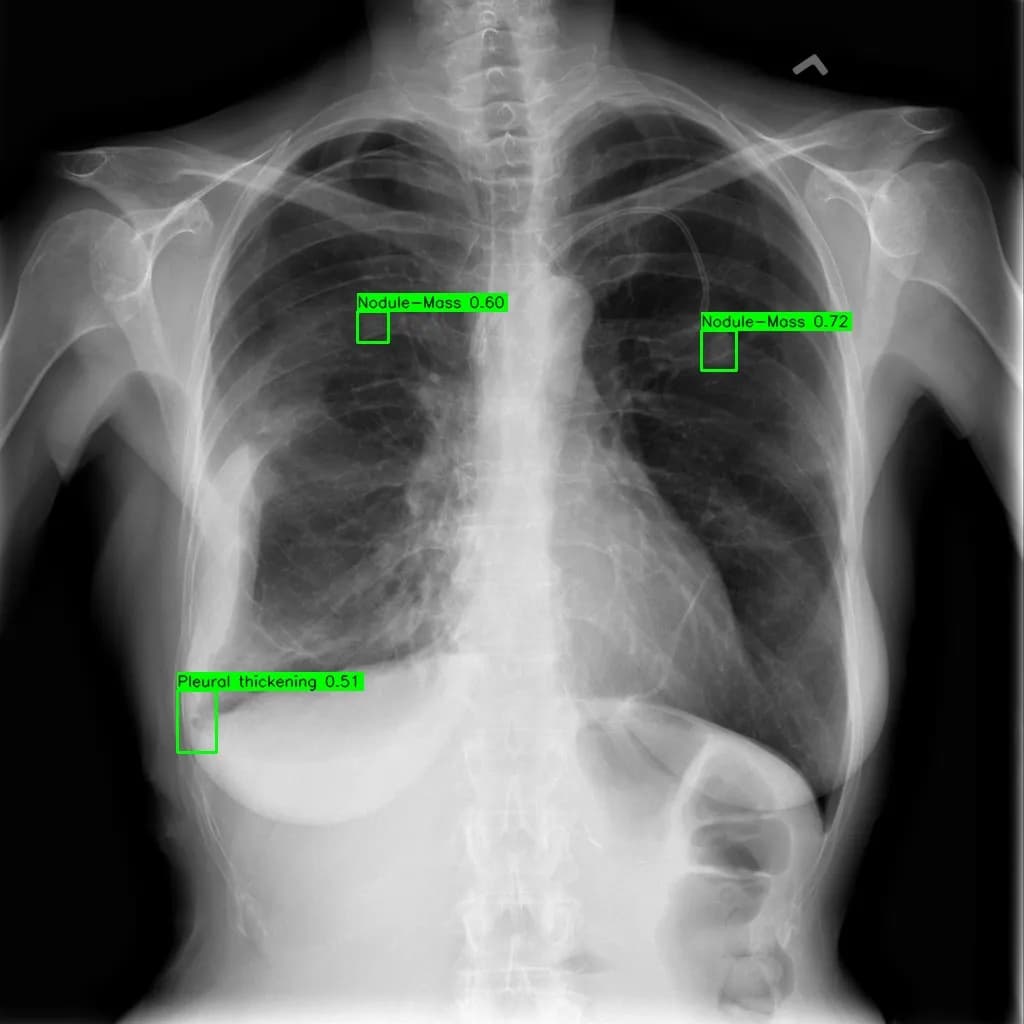

Musculoskeletal X-ray AI Analysis

부위를 클릭하여 결과 이미지를 확인하실 수 있습니다.

씨엔티테크가 주관한 데모데이에서 워크원오원이 AI 기반 뼈·관절 X-ray 판독보조 소프트웨어로 최우수상을 수상했다.